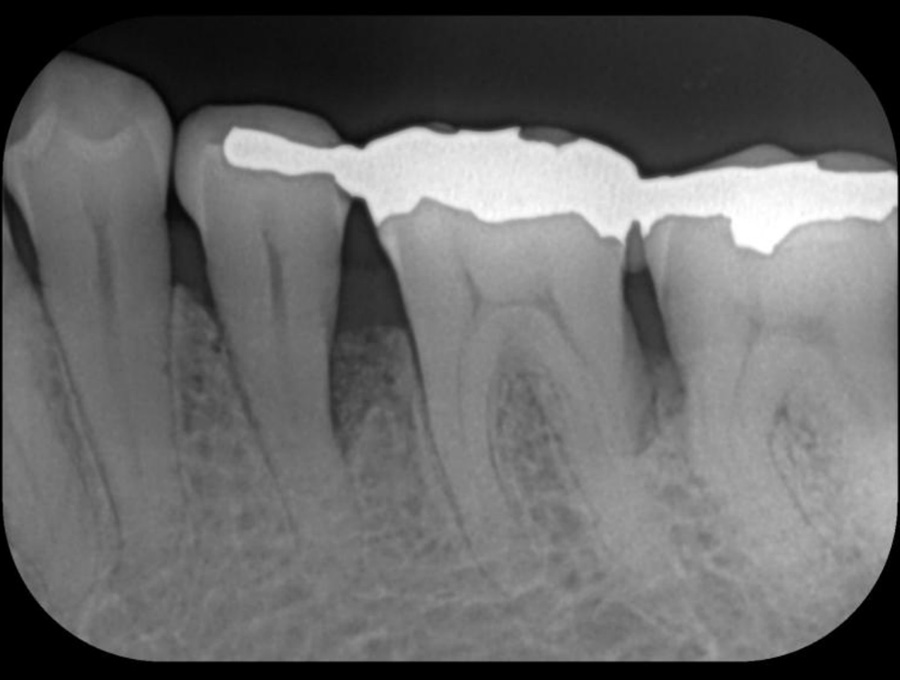

正確な診断

歯周ポケット測定やレントゲン・CT解析など、多角的な検査で歯周病の進行度と原因を正確に把握します。患者さま一人ひとりに最適な治療計画を立て、根拠ある治療につなげます。

精密検査

実際にお口の中の状態をチェックしていきます。レントゲン撮影にて歯や骨の検査を行い、虫歯や治療痕のチェック、歯周病検査などの各種検査を行い、総合的な診断を下します。